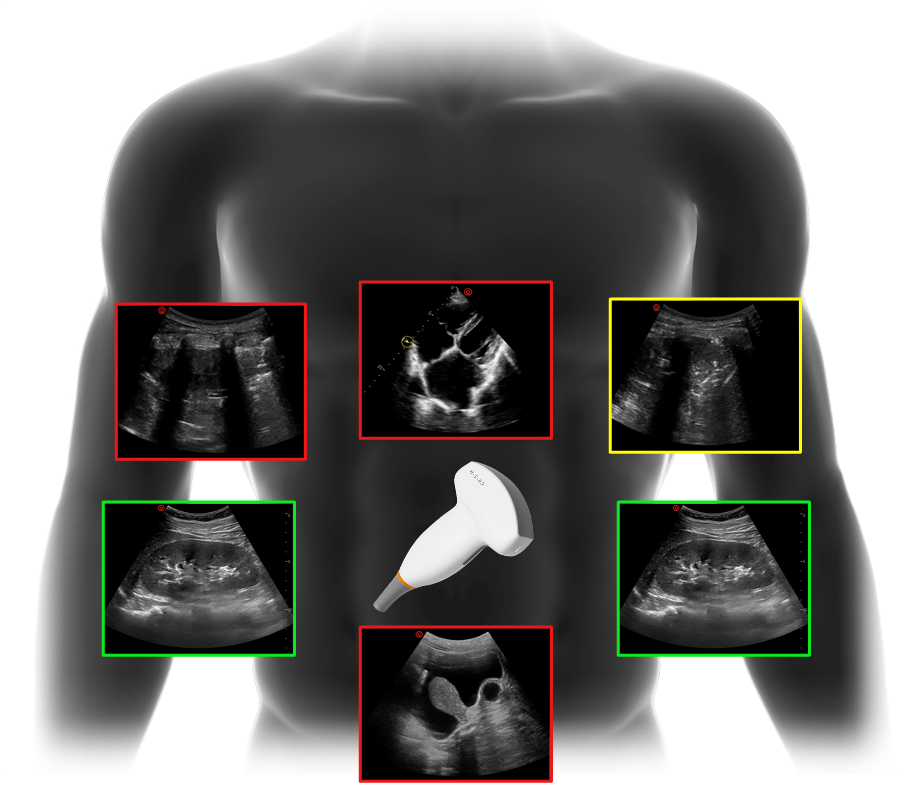

smart emergency solutions powered by ai

enhanced with smart wical toolkit for for faster, more confident decision-making

• auto vti

• auto ivc

• auto diaphragm

• auto vascular

• auto volflow

comprehensive probe selection

a versatile range of transducers designed to support cardiac, lung, abdominal, vascular, and musculoskeletal imaging

• optimized for adults, pediatrics and neonates

• tailored to meet multi-site diagnostic needs in emergency care

• enabling fast, accurate evaluations when every second counts